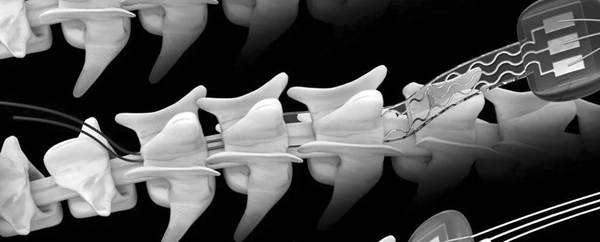

स्विटज़रलैंड के लोज़ान युनिवर्सिटी हॉस्पिटल और स्विस फेडरल इंस्टीट्यूट ऑफ टेक्नालॉजी ने एक ऐसी डिवाइस बनाने में सफलता हासिल की है, जिसकी मदद से कमर के नीचे के हिस्से में लकवे का शिकार हुए तीन मरीज़ चल पाए हैं। इस ऐतिहासिक सफलता सम्बंधी रिपोर्ट जर्नल नेचर मेडिसिन में प्रकाशित हुई है। यह प्रयोग 29 से 41 वर्ष की उम्र के तीन ऐसे लोगों पर किया गया था, जो लंबे समय से व्हील चेयर पर थे। इनमें से एक व्यक्ति मिशेल रोकंति की रीढ़ की हड्डी में इलेक्ट्रोडयुक्त डिवाइस लगाया गया। इसकी मदद से जल्द ही मिशेल ने अपने पैरों पर खड़े होना तथा बाकी दो ने तैरना तथा साइकिल चलाना तक शुरू कर दिया है।

इस तरह तीन व्यक्तियों के एपिड्यूरल स्पेस में कुल 16 इलेक्ट्रोड डिवाइस लगाए गए। ये इलेक्ट्रोड, पेट की त्वचा के नीचे प्रत्यारोपित एक पेसमेकर से दिमाग को संदेश पहुंचाने के साथ शरीर के विभिन्न अंगों तक उन्हें प्रेषित करने का काम करते हैं। जब इलेक्ट्रोड की मदद से दिमाग की तंत्रिकाओं को कोई संदेश मिलता है तो शरीर की मांसपेशियां फिर से सक्रिय होकर कार्य करना शुरू कर देती हैं। इस डिवाइस को आर्टिफिशियल इंटेलिजेंस सॉफ्टवेयर द्वारा नियंत्रित भी किया जा सकता है।